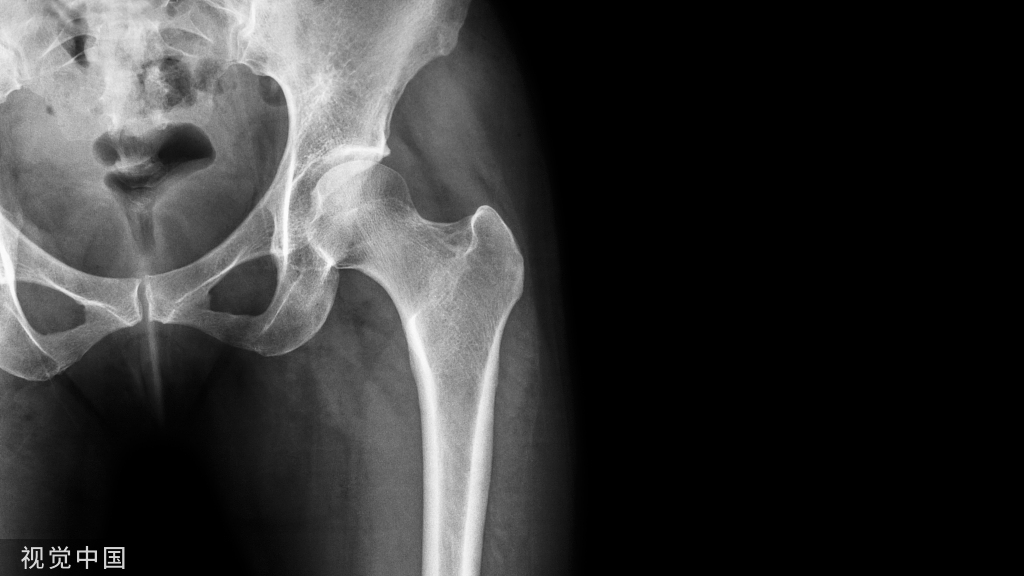

踝关节手术

在患者入手术室后,行无菌铺单前对健侧肢体C臂机透视,并将图像保存于右侧显示屏。若术中需要在垫高状态下进行,则此时应该将健侧肢体垫高透视,尽量做到与术侧肢体一致。当获得满意的正侧位图像后,用薄的描写纸或透明胶片覆盖显示屏图像,并用记号笔对健侧骨骼形态进行临摹。此时我们就获得了患者健侧骨骼轮廓,将其翻转,以此作为标准,对于术中指导和术后检验复位均起重要作用。具体如下图:

上图左侧为健侧标准前后位X片,右侧为临摹的骨骼轮廓。